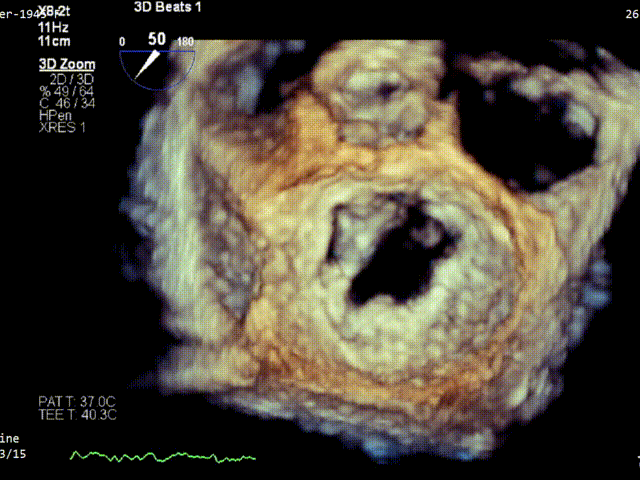

术前3D VIEW

经食道超声提示,患者二尖瓣P1 commissural脱垂、腱索断裂合并重度反流(Carpentier II型/DMR4+)。

二尖瓣后瓣环明显钙化;主动脉瓣轻度钙化;三尖瓣中度功能性反流(FTR2+)。左房明显扩大;左室壁非对称性肥厚,以室间隔基底段肥厚为著(HOCM)。左室整体收缩功能正常。

二尖瓣环AP径33mm,二尖瓣后瓣环明显钙化,房间隔拟穿刺高度40mm;二尖辦脱垂宽度5.7mm,脱垂高度7.7mm,二尖瓣1区前叶长度29mm,后叶长度19mm,二尖瓣2区前叶长度23mm,后叶长度14mm,MVA=4.0cm²。